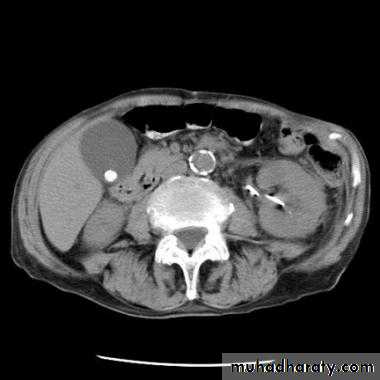

Acute pancreatitis

The pancreas is usually enlarged, often diffusely with irregular outlines due to extension of inflammatory process into the surrounding fat. There may be low density areas at CT or echo-poor areas at US (edema and necrosis)

The diagnosis is usually made on clinical and biochemical grounds, the purpose of CT is to assess the severity and complications:

1.pancreatic necrosis (areas with no enhancement)

2.abscess appear as fluid collection which may contain gas

3.vascular complications e.g. splenic vein thrombosis, arterial erosion & pseudoaneurysm

4.pseudocysts occur as a result of leak of pancreatic secretions that are contained in a cyst like manner within and adjacent to the pancreas.

They can be demonstrated with CT or US as thick or thin walled cysts of variable sizes.

Many pseudocysts resolve in the weeks following an attack of acute pancreatitis, some persist and may need surgical or percutaneous drainage.